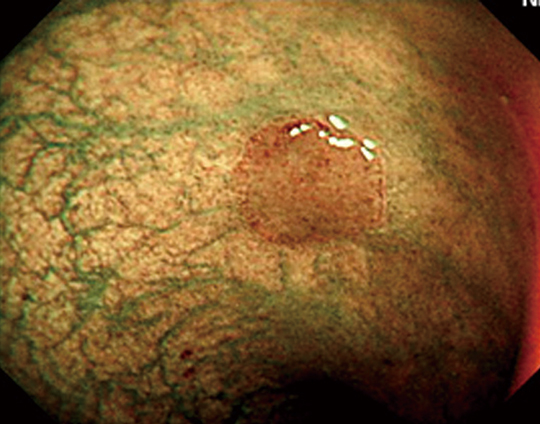

Example of tissue observation in ordinary light

Example of tissue observation using NBI

*2: Narrow Band Imaging (NBI)

By imaging the affected area using two colors in specific narrow bands of wavelengths, the fine structures of the capillaries and mucous membranes are emphasized.